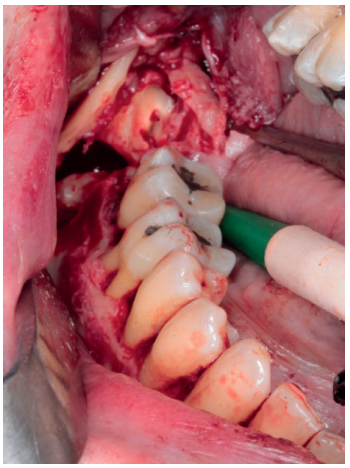

A nivel local, se anestesiaron los nervios alveolar inferior y bucal mediante articaina 40mg/ml con 0.01 mg/ml de epinefrina (Ultracain® , España). Se realizó una incisión intrasulcular a espesor total con una descarga distal alta en la rama mandibular que se extendió hasta distal del canino inferior izquierdo sin necesidad de realizar una descarga en este punto. Se despegó el colgajo con la ayuda de un periostotomo para poder acceder a la superficie ósea. Con pieza de mano y fresa redonda de carburo de tugsteno se realizaron tres cavidades equidistantes: la primera a la altura del trígono retromolar (Figura 5), la segunda apical a los premolares inferiores derechos y la tercera mesio-apical al canino inferior derecho. Dichos accesos permitieron abordar y despegar toda la lesión en su extensión para posteriormente poder traccionar de ella a través de la cavidad media (Figuras 6 y 7). La cavidad posterior sirvió también para realizar la exodoncia del cordal (Figura 8). Tras la eliminación del quiste se llevó a cabo un legrado minucioso de la cavidad remanente y se limpió con agua oxigenada. A continuación, se colocó la mini placa con una extensión desde la rama mandibular hasta mesial de la cavidad media. Por último, se reposicionó el colgajo y se suturó de forma hermética mediante una sutura poliamida recubierta no reabsorbible de 4/0 Supramid (Aragó® ) (Figura 9). La muestra obtenida se conservó en formaldehido al 10% y se envió al anatomopatólogo, el cual confirmó el diagnóstico de quiste dentígero sin displasia celular (Figuras 10 y 11).